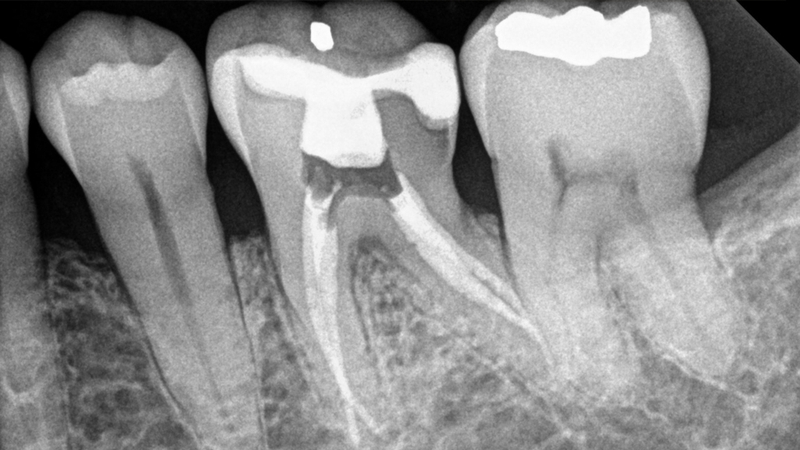

Tuy nhiên, răng hàm và răng bị nhiễm khuẩn sẽ phải lấy tủy răng từ 2 lần trở lên. Bởi vì răng hàm có nhiều ống tủy trong chân răng nên không thể lấy xong chỉ trong một lần. Đối với răng bị viêm nhiễm, các bác sĩ sẽ phải khử khuẩn trước thì mới thực hiện hoàn tất quy trình.

Trong lần hẹn gặp đầu tiên, bệnh nhân sẽ được bác sĩ đặt thuốc diệt tủy răng. Loại thuốc này sẽ giết chết vi khuẩn có hại trong răng. Bên cạnh đó, bạn sẽ được định hình ống tủy để thuận tiện cho việc lấy tủy lần sau.

Khi bệnh nhân đến lấy tủy răng lần 2, bác sĩ sẽ lấy tủy răng và thực hiện các biện pháp bảo vệ răng như hàn trám và bọc sứ. Nếu bác sĩ có tay nghề kém không thể lấy hết tủy răng trong một lần, bệnh nhân sẽ phải quay lại lấy tủy răng mấy lần nữa.